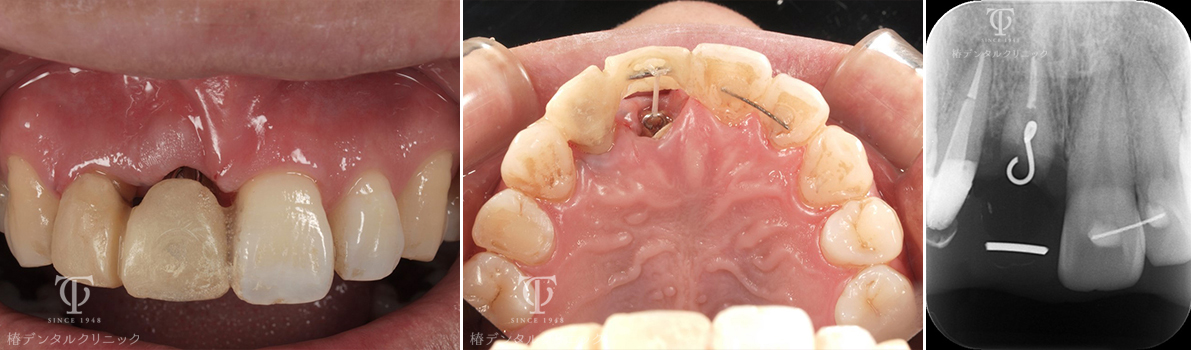

Case05

歯根破折の為、前歯が位置異常をおこしていました。

残った歯を部分矯正治療で引っ張り硬組織・軟組織を再生させました。

術前

術後

- 症状

- 前歯を綺麗にしたい

- 治療期間

- 約1年半

- 治療費用

- 部分矯正治療:330,000円×2

インプラント治療:473,000円

オールセラミッククラウン:165,000円

歯根破折をおこし前歯が位置異常をおこし綺麗にしたいということで来院されました。残った破折歯を部分矯正治療に利用して骨造成を回避しました。

【リスク・副作用】

インプラント治療後、痛みや違和感、出血、腫れなどが出る事があります。喫煙者、糖尿病などの方の場合、歯が生着しない場合があります。